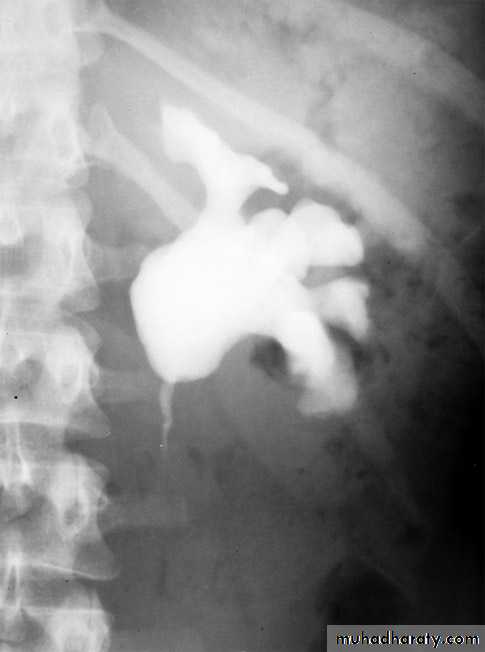

Infantile hydronephrosis ( PUJ OBSTRUCTION ):

IVU shows :

Marked dilatation of pelvis and may be extra-renal.

Calyceal dilatation is late and in advanced cases form foot shape PCS

The ureter is not seen and when it is seen looksnormal .

Delayed film with I.V. diuretic produce gross dilatation .